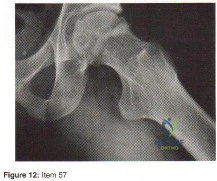

- fracture of the acetabulum

- protrusion of the acetabulum

- inadequate inferior coverage

- inadequate superior coverage

- inadequate anterior and posterior coverage